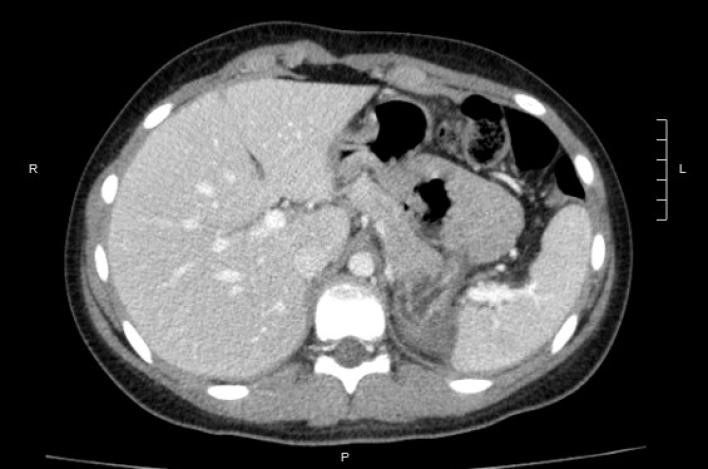

Se realizó tomografiía computarizada de control sin evidencia de lesiones residuales ni sitios isquémicos, constatado por la captación de contraste endovenoso en todo el volumen del órgano remanente (Figura 5 y Figura 6). La paciente se encontraba asintomática hasta el último control.

Figura 5: Tomografía computarizada de control. Corte axial